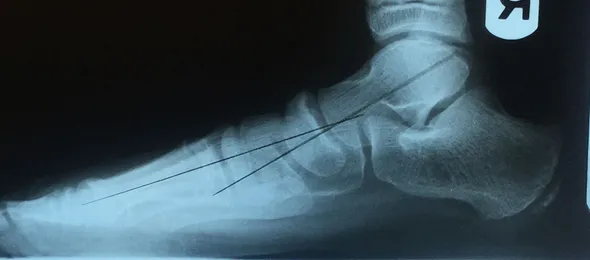

Pre and Postop X-rays Subtalar Joint Implant (Below)

Pre and Postop Subtalar Implant and Percutaneous Achilles Lengthening Below. The first pics show wedging of the distal tibia physis causing ankle valgus due to constant pressure caused by the severity of the flatfoot (JT)